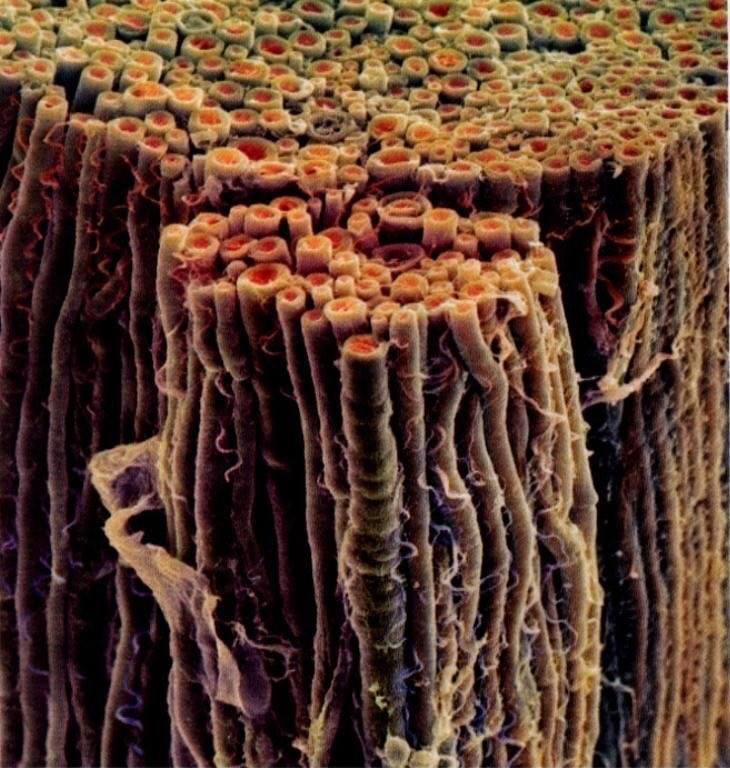

Hasta hace poco, se veía el sistema nervioso periférico como meros cables de unión que transportaban información. Hoy en día, lo vemos como tejido vivo: Si lo cortamos, no se va el dolor, paradógicamente, la sensibilidad a veces se exacerba, a veces. Desafortunadamente esta información ha llegado demasiado tarde para las neurotomías realizadas en los 60 y 70s. Incluso en las simpactectomías, las fibras aferentes pueden desarrollar sensibilidad a la adrenalina.

La próxima vez que veas ballet, cualquier deportista o contorsionista, imagínate las demandas físicas del sistema nervioso y maravíllate con su adaptabilidad de moverse, doblarse y estirarse. Este concepto de la biomecánica del sistema nervioso, o como Michael Shacklock denominó en 1995, "neurodinamica", es un concepto relativamente nuevo. Neurodinamia es algo más que ejercer tensión, es un concepto que nos ayuda a unir conceptos meramente mecánicos a términos fisiológicos de plasticidad neural. El objetivo del tejido neural es lograr que haya una comunicación óptima en todas las situaciones. Ahora, se sabe más sobre la complejidad de esta comunicación electroquímica en una estructura que es sensitiva, reactiva y plástica, que está contínuamente doblándose, estirándose y adaptándose. El tejido conectivo del sistema nervioso, envuelve a las neuronas y la glia para brindar protección a la misma, tanto de sustancias químicas como de fuerzas indeseadas. Ese tejido conectivo, está conectado desde el craneo, columna vertebral, filum terminale y la cobertura de los nervios periféricos. El tejido conectivo tiene conexiones con otros tejidos (Butler, The Sensitive Nervous System), que pueden explicar por qué el dolor de cabeza puede estar relacionado con el coxis:

El tejido conectivo no está distribuido equitativamente, ya que el tejido del nervio cubital, puede ser del 21%, pero el tejido conectivo del ciático es del 81%.